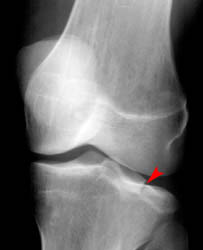

Lateral Tibial Plateau Fracture

• When depression is not present, fracture may be difficult to recognize with standard radiographic exam. Alternative views and/or CT may be required for diagnosis.

• CT with multiplanar reconstruction (MPR) can be useful to help understand the anatomy of the fracture in 3D.